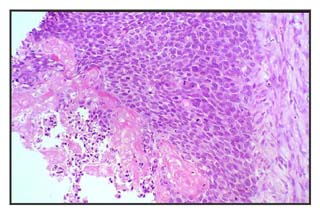

Figura 3: Células neoplásicas en progresión hacia células fantasmas. Diferenciación matricial.